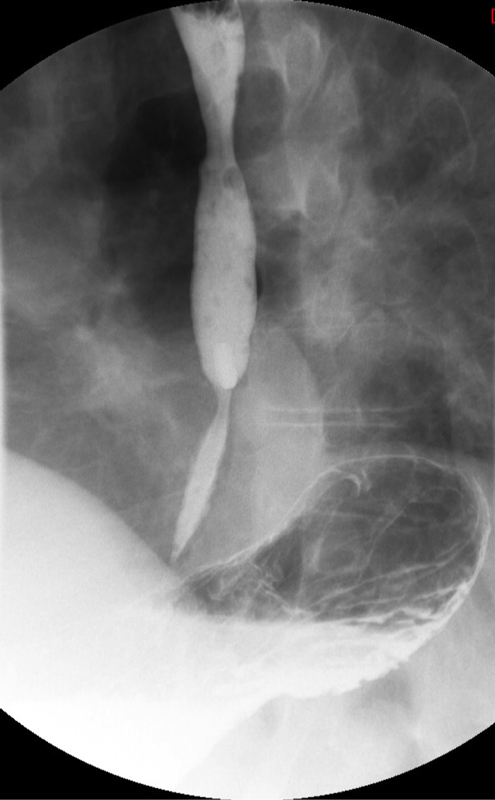

- Method—Thoracic:

- With the patient standing upright, have them turn into a left posterior oblique position.

- Instruct the patient that you will be handing them a cup containing a small amount of water and effevescent crystals and that they should drink it as quickly ask possible.

- As soon as the patietn has finished the water, exchange the empty cup for a cup of thick barium.

- Ask the patient to drink two (2) sips of thick barium. The patient does not need to drink this quickly.

- After the patient has begun drinking, take images of the upper and lower esophagus distended and coated with barium

(key image 5)

(key image 6)

(key image 7).

- Thoracic images are obtained in the upright RPO and LPO projections after the adminstration of bubbly barium (EZ Gas followed by thick barium).

- The goal of these images is to see the thoracic esophagus distended and coated with barium. This may not be possible with one image and make take several to accomplish.